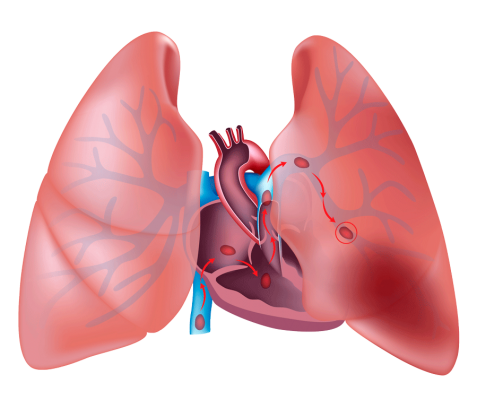

La tromboembolia pulmonar (TEP) se refiere a la obstrucción de la circulación arterial pulmonar debido a la presencia de trombos que se han formado en otros lugares del sistema venoso, generalmente en las venas de las extremidades inferiores. Estos trombos pueden desprenderse y viajar a través de la circulación sanguínea hasta llegar a los vasos sanguíneos del pulmón, donde pueden obstruir el flujo de sangre y causar daño en los tejidos pulmonares.

Cuando un trombo se desprende de la vena donde se formó, viaja a través de la circulación sanguínea hasta llegar a las arterias pulmonares, donde puede ocasionar una obstrucción parcial o completa. Esto impide que la sangre llegue adecuadamente a los pulmones para su oxigenación, lo que puede resultar en una disminución en el suministro de oxígeno al organismo y un aumento en la presión en la arteria pulmonar. En casos graves, la TEP puede provocar insuficiencia respiratoria aguda, fallo cardiaco y, en algunos casos, puede ser potencialmente mortal.